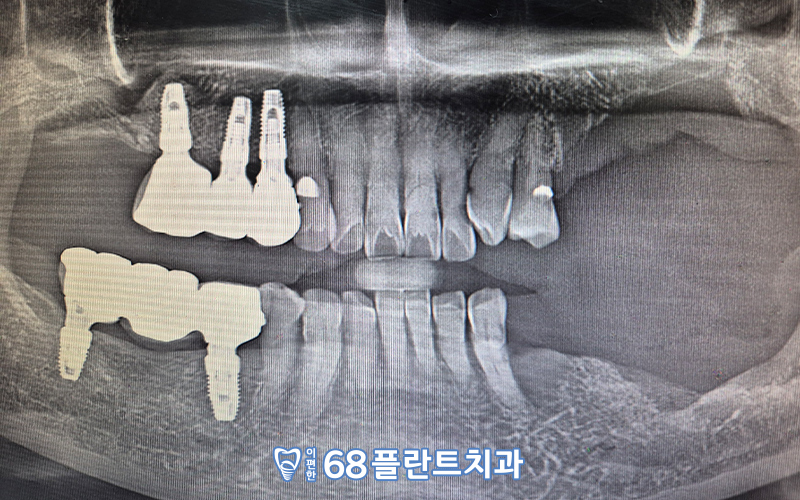

이렇게 뼈이식을 병행한

임플란트 치료를 통해

양측으로 편안하게 식사하실 수 있도록 도와드리고,

환.자분께 만.족감을 드릴 수 있었던

치료 사례를 소개해드렸는데요.

수술 전 CT 사진을 통해,

잇몸뼈의 양, 인접치들과의 관계,

상악동과 신경관의 위치 등

여러가지 구강 내 상황을

면밀하게 체크한 후

식립할 위치 및 방향을 사전에 계획하여

수술을 진행하였습니다.